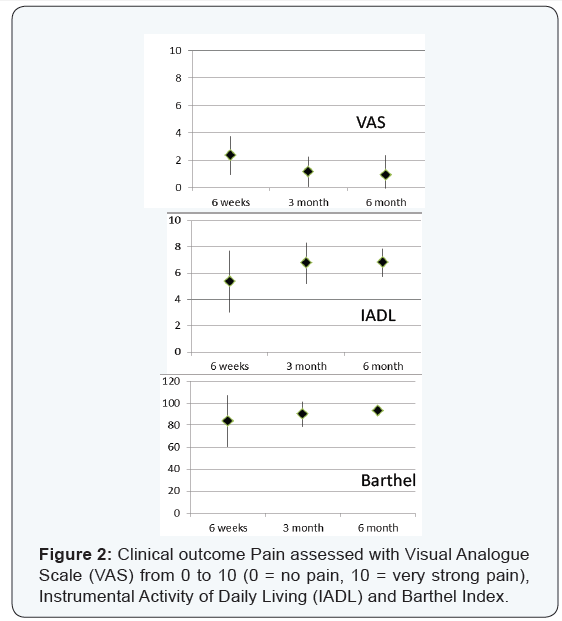

Data gathered from medical records included posttraumatic status and findings from radiographs. Assessment tools such as VAS (Visual Analogue Scale, from 0 to 10, 0 = no pain, 10 = very strong pain), the Barthel Index and Instrumental Activity of Daily Living (IADL) were used to document indicators postoperatively at 6 weeks, 3 months and 6 months (Figure 2). Conventional radiographs were done postoperatively at 6 weeks, 3 months and 6 months. To confirm complete fracture healing, an additional CT scan of the pelvis was done after 6 months (Figure 2). Additionally, factors such as the delay to surgery, time of operation, duration of the hospital stay, complications and the need for orthopaedic hardware removal were extracted from the records.

Patient satisfaction

Scores from clinical assessments are provided in (Figure 2). There was a statistically significant improvement in the scores of IADL and Barthel Index between the 6 week follow up and the final assessment after 6 months (IADL p=0.03, Barthel Index p= 0.01). Three patients complained of pre-traumatic iliosacral and lumbosacral pain due to previous iliosacral arthritis and lumbosacral anterolisthesis. At the final 6 month follow up assessment, 7 patients had no residual pain (mean VAS0.9, SD± 1.3, range 0 to 4). 12 patients were satisfied and very satisfied with the result and would do the operation again.